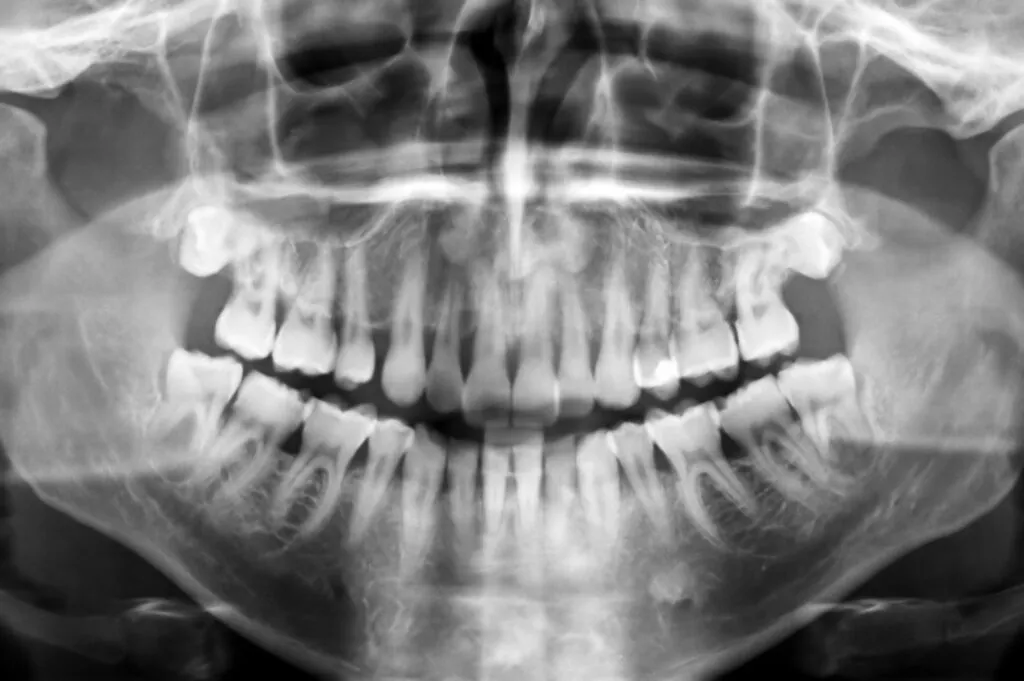

Pediatric dentists use X-rays to aid in diagnosing disease or damage that isn’t visible during a normal dental exam.

X-rays help catch oral conditions and diseases early, such as cavities and gum disease. They aren’t usually taken every six months unless a child has a high disease risk.